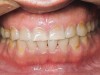

Figure 13  Adolescent triad: A 16-year-old with pathologic wear on incisors and a loss of tooth texture from erosion and abrasion. Medical history was indicative of the triad.

Figure 13